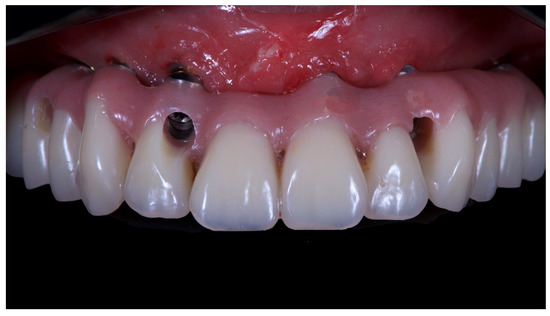

Final prosthesis mounted. Note the through holes. In two cases, it was compensated with only the Seeger, without a through screw.

Figure 14.

Final prosthesis with composite fillings made with pink and tooth-colored composite.

Figure 15.